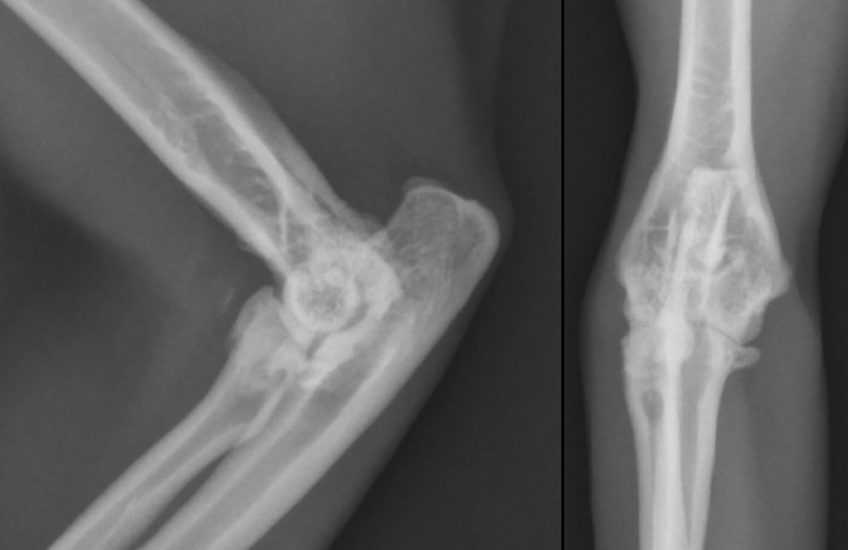

Помочь в выявлении воспалительных процессов могут специальные методы исследования, например, рентгенография. На ней опытный врач-ортопед обнаружит аномалии, свидетельствующие о дегенеративно-дистрофических изменениях в органе, остеофитоз (костные разрастания), припухлость мягких тканей вследствие воспаления.

Рентгенограмма (боковая проекция) локтевого сустава кошки с остеоартритом